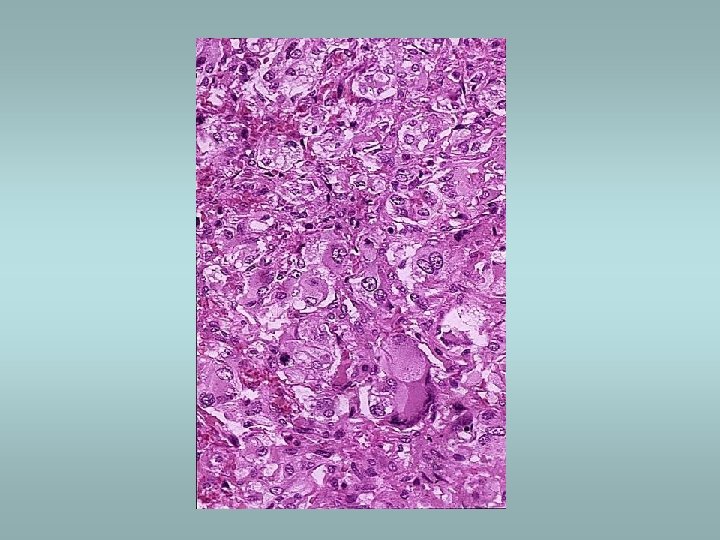

Adrenal medulla Phaeochromocytoma ü Catecholamine production – hypertension ü 85% in medulla (extra-adrenal tumors designated paragangliomas) ü Sporadic (90%) or associated with familial syndromes (MEN, von Hippel-Lindau, von Recklinghausen) ü Histologically – pleomorphism, mitotic activity - however there are no reliable histological predictors of malignancy!! ü Only criterion of malignancy – metastasis Other tumors – neuroblastoma, ganglioneuroma